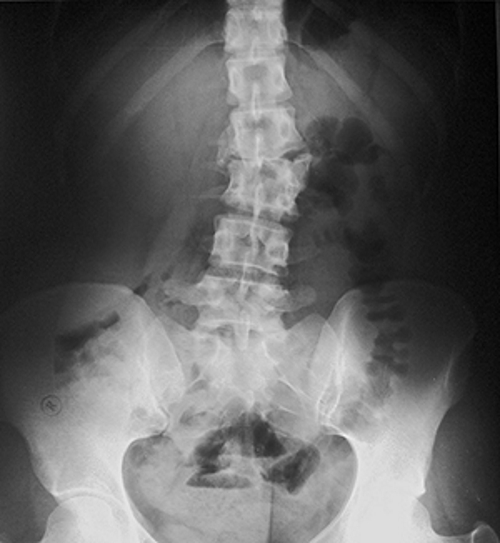

Методы диагностики

Пациентам с симптомами хондроза необходимо пройти обследование у невролога. В некоторых случаях может потребоваться консультация вертебролога, нейрохирурга или хирурга. Врач сначала проводит внешний осмотр и собирает анамнез. Для диагностики применяются лабораторные исследования, включая общий и биохимический анализы крови. Для более детальной оценки состояния позвоночника назначаются следующие методы:

- рентгенография;

- компьютерная томография (КТ);

- магнитно-резонансная томография (МРТ).

Эти исследования позволяют точно установить характер повреждений позвоночника и степень прогрессирования хондроза.